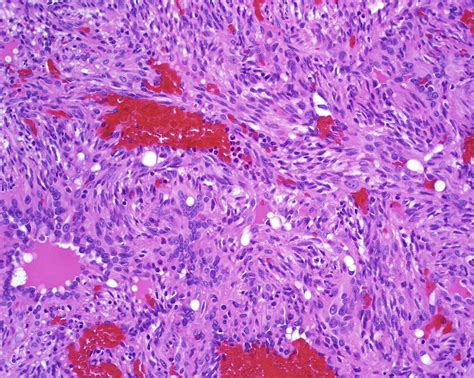

Leiomyosarcoma is a malignant tumor that arises from smooth muscle cells. It can occur in various parts of the body, including the uterus, gastrointestinal tract, and soft tissues. Leiomyosarcomas are often aggressive and can metastasize to other organs. Treatment typically involves surgery, radiation therapy, and chemotherapy.

Synovial Sarcoma

Synovial sarcoma is a malignant tumor that arises from synovial tissue, which lines the joints, tendons, and bursae. It can occur in various parts of the body, including the extremities, trunk, and head and neck. Synovial sarcomas are often aggressive and can metastasize to other organs. Treatment typically involves surgery, radiation therapy, and chemotherapy.